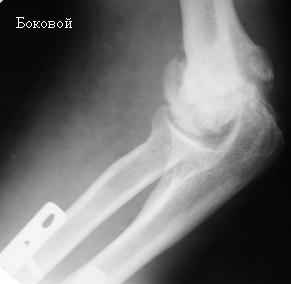

Стойкая комбинированная контрактура правого локтевого сустава

Увжаемые коллеги! На консультации больной со стойкой комбинированной контрактурой правого локтевого сустава.

В прошлом - спортсмен, сейчас охранник. Травма 2 августа 2008г., автодорожная. Оперирован в одной из больниц города. Остеосинтез, два месяца гипс. Объем движений с тех пор не изменился. Боли после физнагрузки (пытается тренироваться).

Имеется ложный сустав мыщелка плечевой кости.

Необходимо выполнить остеосинтез и добится сращения и только потом возможен-артролиз локтевого сустава.